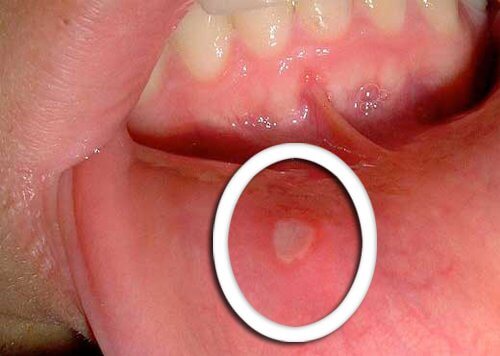

تغيرات ملحوظة في منطقة الفم

تظهر الأعراض المُبكرة لمشكلة سرطان الفم والبلعوم في صورة تقرحات صغيرة لا تختفي أبدًا. وتظهر باللون الأحمر أو الأبيض على اللسان، أو على اللثة، أو الشفتين.

كُن يقظًا عند حدوث أي تغيرات غير معتادة، خاصةً إن لم تتحسن في غضون أيام قليلة، وقم بعرضها على الطبيب.